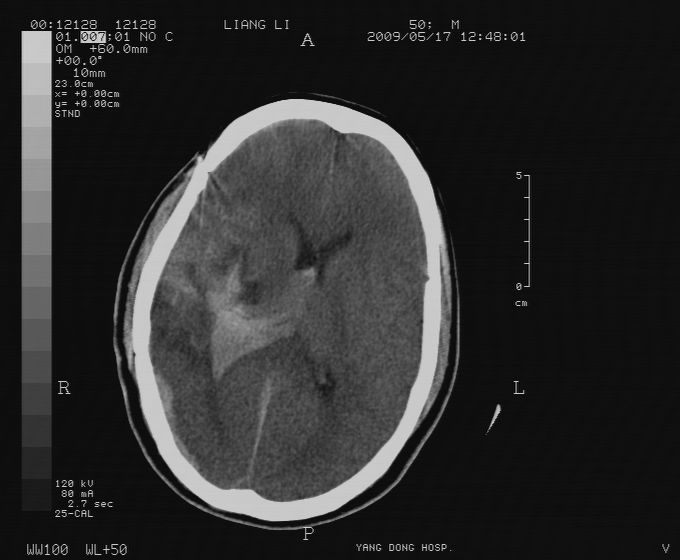

以下是引用zjzjr在2009-5-18 11:26:00的发言:[br]右颞枕叶及基底节区脑出血破入脑室系统,蛛网膜下腔出血,右枕顶部硬膜下血肿.颅骨及颅内低密度软化灶为血肿清除术后改变.

以下是引用随光逐影在2009-5-18 14:47:00的发言:[br]支持 右颞枕叶及基底节区脑出血破入脑室系统;蛛网膜下腔出血;右枕顶部及右侧天幕硬膜下血肿。右侧颅骨术后改变;颅内低密度软化灶为血肿清除术后改变。